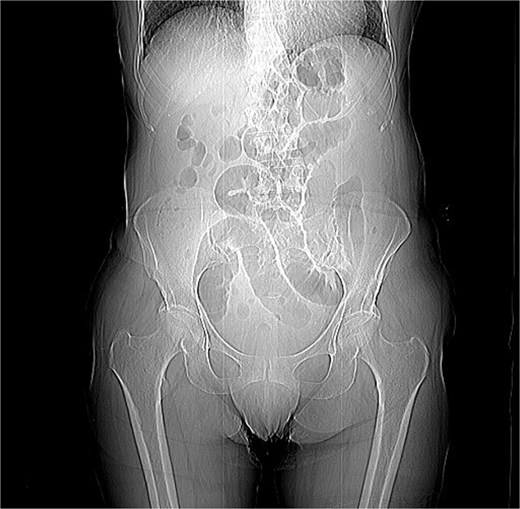

Imaging plays a central role in the diagnosis of intussusception. Abdominal computed tomography (CT) with contrast is considered the gold standard due to its high sensitivity and specificity. In adult cases, CT typically shows the characteristic “target” or “sausage-shaped” mass, which reflects the telescoping of one bowel segment into another [4].

Intussusception is described as the telescoping of one bowel segment with its mesenteric fold into an adjoining bowel tract, causing venous congestion and blood supply reduction. Intussusception can occur anywhere along the small and large bowel. This condition in adults poses diagnostic and therapeutic challenges due to its rarity and the nonspecificity of symptoms. Most adult cases are associated with an underlying lesion, often neoplastic, benign [8] or malignant (metastatic lesions, lymphomas, and adenocarcinomas), which underscores the importance of surgical resection and histological analysis [5]. The use of contrast-enhanced CT has greatly improved the preoperative diagnosis of intussusception, allowing for early and accurate identification of the condition. CT scan shows a peculiar sign, described either as “target,” “bulls- eye,” or “sausage-shaped” lesion (Fig. 3). This pathognomonic sign can be identified at coronal and axial view [5]. This case emphasizes the need for a high index of suspicion in elderly patients presenting with bowel obstruction and nonspecific abdominal symptoms. Prompt surgical intervention, as performed in this case, is crucial to prevent complications such as bowel ischemia or perforation, which significantly increase morbidity and mortality. Moreover, in this case, an underlying potentially malignant evolving condition was discovered and removed. Given the patient’s overall clinical status and the urgency of the situation, the choice of surgical management was appropriate.